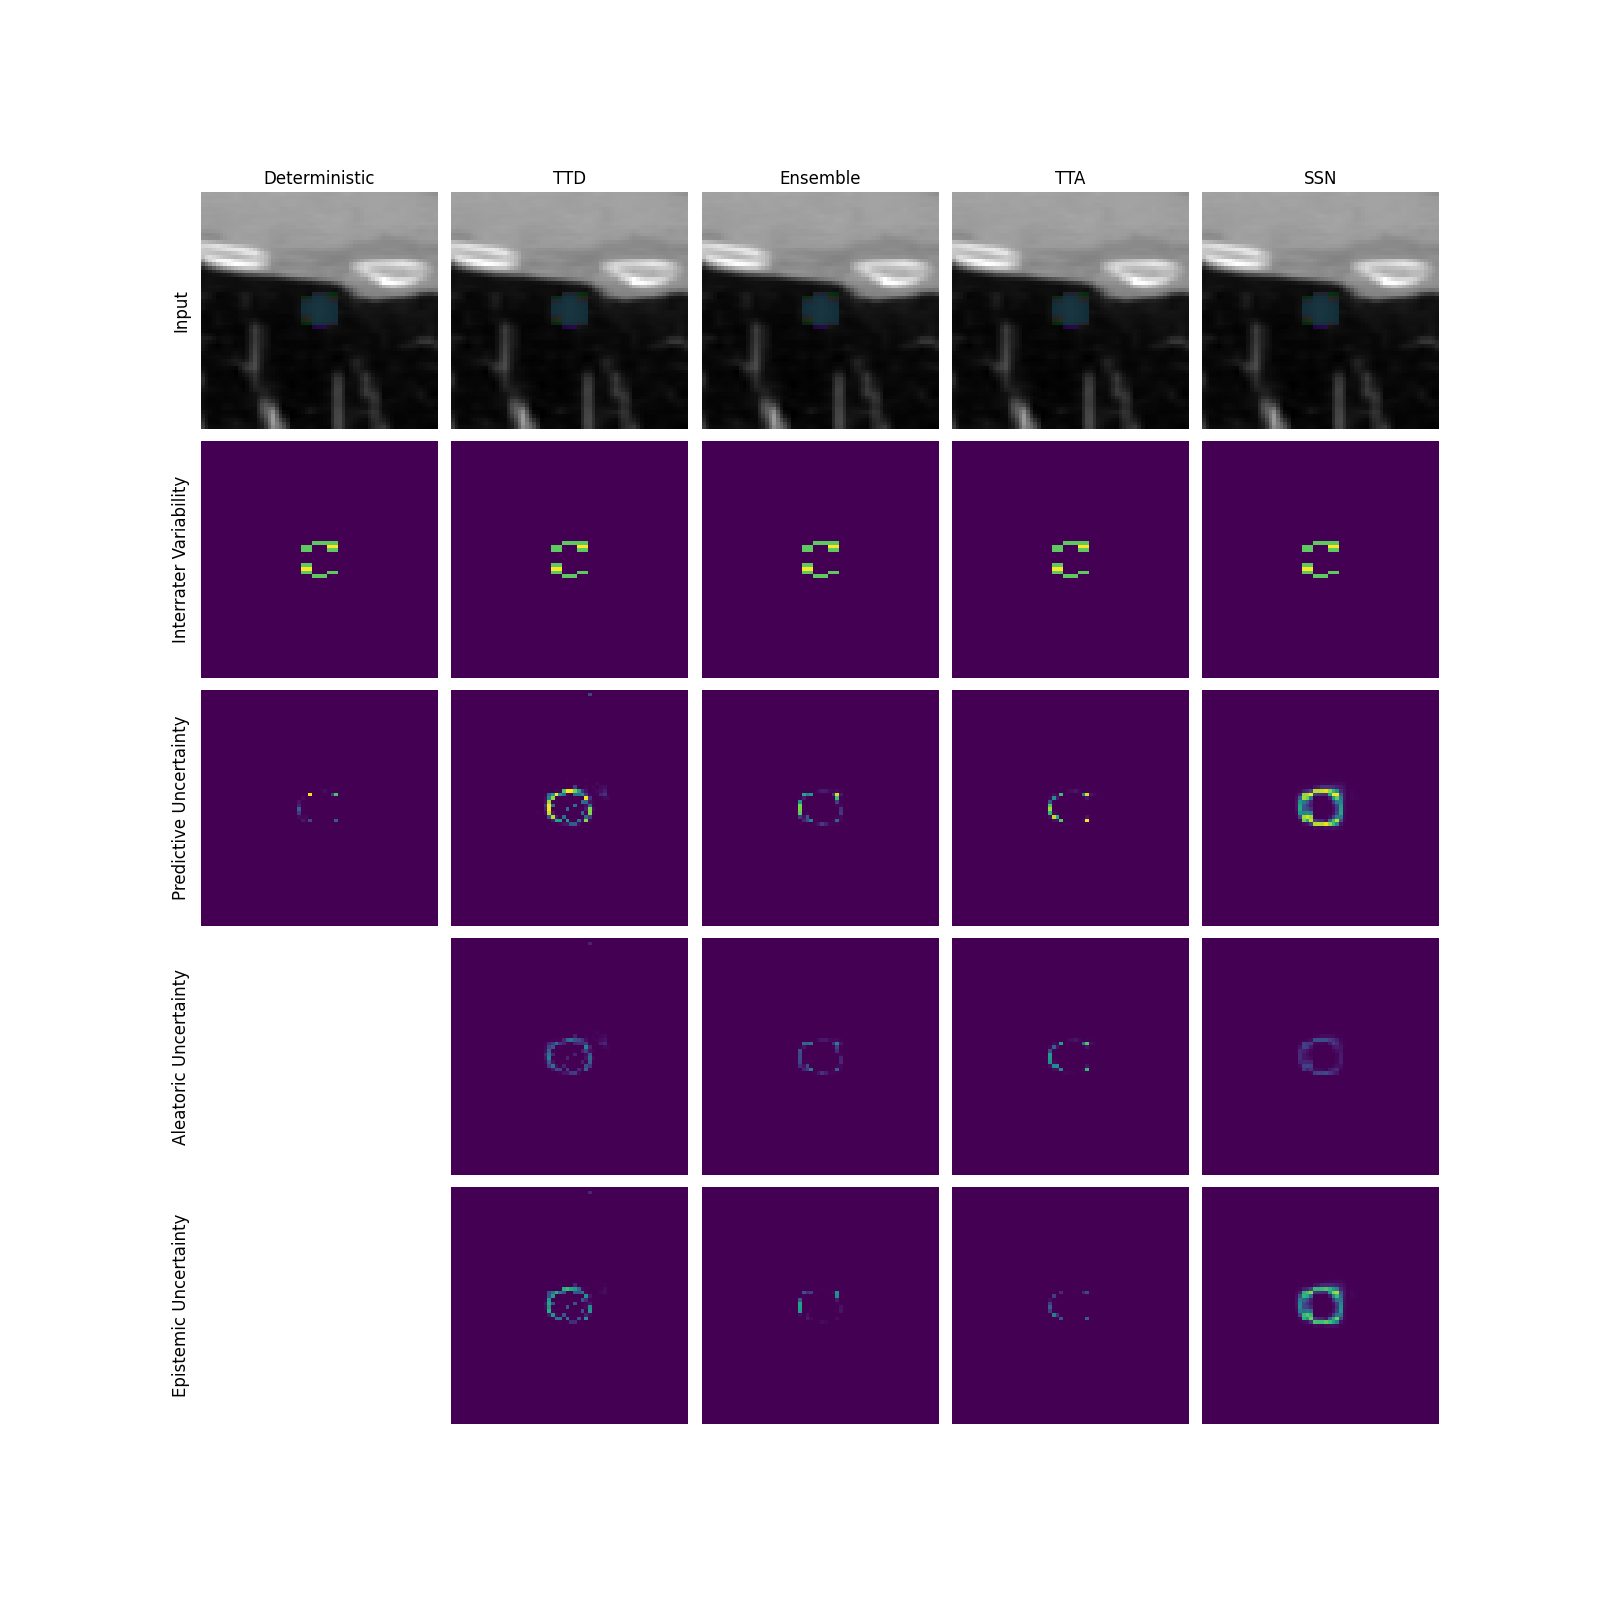

Q1 + Q2: For assessing the capability of uncertainty methods in capturing AU, we employ the normalized cross-correlation (NCC) as a quantitative measure between the predicted uncertainty map and the reference uncertainty map based on the disagreement of multiple raters (for details see Appendix A). Additionally, we perform qualitative inspections of the uncertainty maps. Based on the theory, successful separation of uncertainties would imply AU-measures to exhibit high NCC and high qualitative fidelity (Q1 = ”yes”) and vice versa for EU-measures (Q2 = ”no”).

The general findings of the uncertainty separation study are summarized in Figure 2a, while underlying results are shown in Figure 2b for the toy dataset and Figure 3 (see gray-shaded ”Q” indicators on respective panels) for LIDC and GTA5/CS. More detailed descriptions and results as well as a qualitative analysis of uncertainty maps are provided in Appendix G.

Modeling aleatoric uncertainty (Q1 + Q2) While AU-measures clearly captured AU much better than EU-measures for the toy dataset, this behavior is inconsistent on the real-world datasets. On the LIDC datasets with AU stemming from rater ambiguity, which mostly occurs at the border of structures, the benefit of separating AU-measures from EU-measures is not evident when examining the NCC scores. For GTA5/CS, where induced label ambiguities span entire spatial structures, the AU-measures generally capture AU better than EU-measures. However, the absolute NCC scores from the AU-measures vary greatly across prediction models. We attribute this to SSNs capturing the widespread label ambiguities, while other models overemphasize the border regions.

Modeling epistemic uncertainty (Q3 + Q4) While EU-measures capture EU better than AU- and PU-measures on all datasets, the benefit of this separation varied greatly depending on the AU in the respective training and test data. More specifically, when more AU is present in the i.i.d. training and test data, the benefit of EU- over AU- and PU-measures increases as the ambiguity modeling in the i.i.d. setting is separated from the EU-measure. This connection can also be observed on GTA5/CS, where the captured AU induced by spatially widespread ambiguities translates to a higher EU-measure performance compared to LIDC.

General Insights. Although both, AU- and EU-measures, mostly do behave as expected, the extent of achieved separation depends on the data set properties such as the presence of ambiguities in i.i.d and/or OoD cases. As theoretically motivated in Appendix E, we observe that TTA is in fact most suited for modeling EU, resolving a controversial debate in current literature. We base this on the behavior of our derived EU-measure for TTA being very similar to ensembles and TTD, often even outperforming TTD. The comparable performance to ensembles renders TTA often a cheap alternative for estimating EU. For SSNs, our proposed EU- and AU-measures perform as intended on the toy dataset and GTA5/CS. Whereas on LIDC, the ambiguity, which is mostly present in the border regions, seems to be captured by EU-measures.